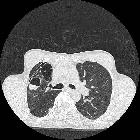

Kartageners

syndrome. Cystic bronchiectasis in both lungs with predominance in lower lobes. Few centrilobular micro nodules representing mucoid impaction with few areas of ground glass opacities are seen in the left lower lobe.

Cystic bronchiectasis is one of the less common morphological forms of bronchiectasis. It may be present on its own or may occur in combination with other forms of bronchiectasis.

It is characterized by saccular dilatation of bronchi that extends to the pleural surfaces. When aggregated these may give a "bunch of grapes" like appearance.